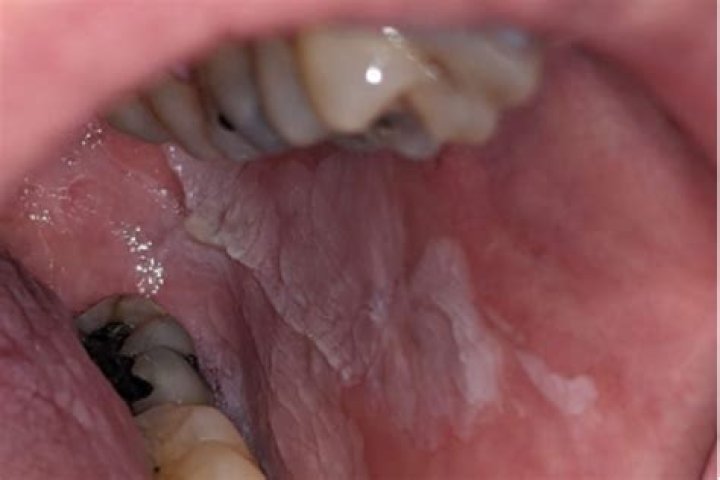

A case of subclinical OHL and candidiasis was identificated in a DM patient by cytopathologic analysis. PCR results demonstrated EBV-DNA in 65% of the pre...